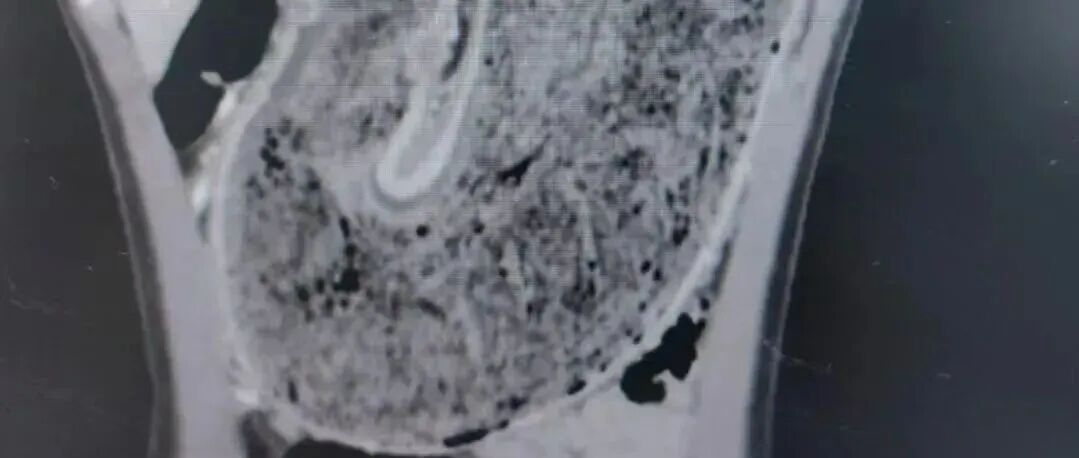

可怕!11岁女孩胃部完全被它占据......